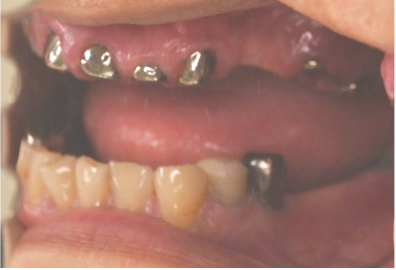

After

【義歯を装着したところ】

【義歯を外したところ】